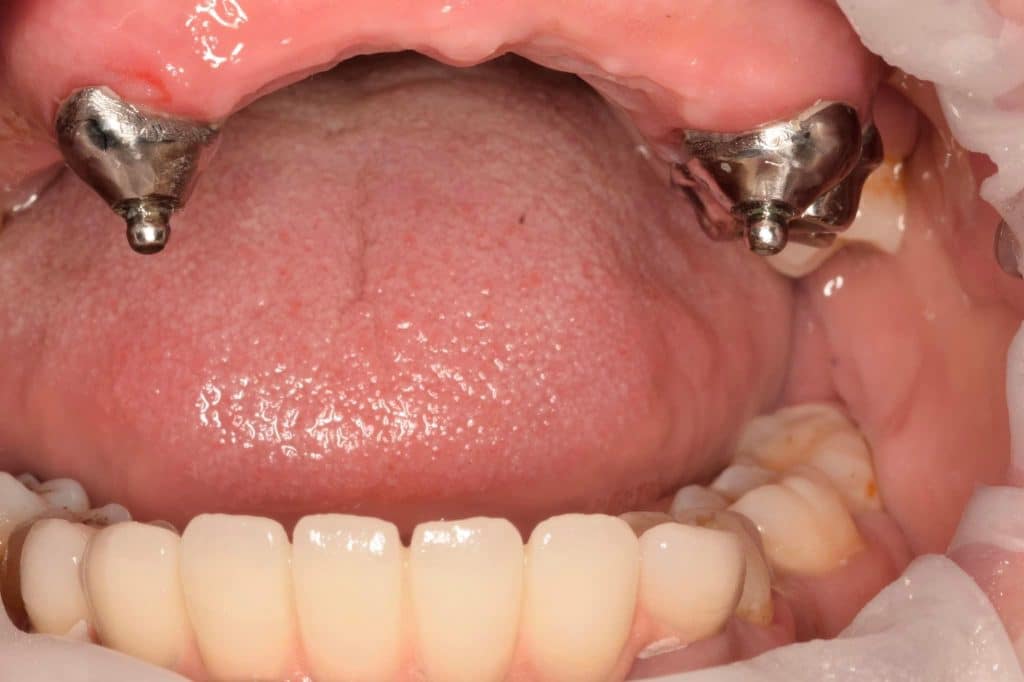

the midline and canine line was marked on wax rim inside the patient’s mouth. After that teeth selection and shade matching were done according to patient’s facial profile and aesthetic needs. Teeth arrangement was done and temporary denture was tried for esthetics, phonetics, retention and stability. Flasking and dewaxing were carried out for the final denture. During packing of the final denture, secondary coping was placed on its position on the cast and it was done with heat cure acrylic resin material. The beads present on secondary coping wouldhelp in mechanical retention within the denture.

Female part of ball and socket attachment was placed using self cured acrylic resin

6th clinical visit:

Finished and polished denture was inserted into the patient’s mouth and Occlusion was checked.